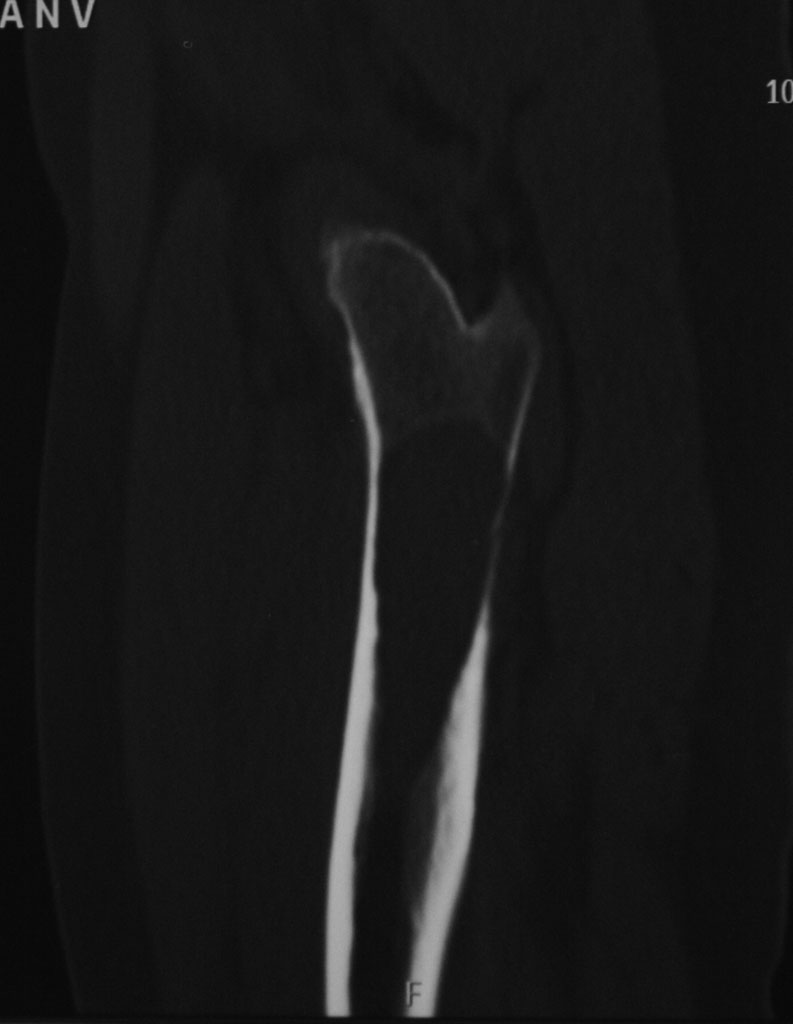

Гистологическое заключение: участки остеонекроза,хроническое воспаление. На этой неделе больная обратилась с жалобами на боли в области левого тазобедренного сустава. Со стороны оперированной ноги жалоб нет. Проведенное рентгенобследование выявило наличие полостного образования в проксимальном метадиафизе левой бедренной кости, перелом наружной стенки. Планируем выполнить БИОСлевой бедренной кости по методике аналогичной на правой ноге и этому случаю Какой фиксатор выбрать: длинную гамму или универсальный бедренный гвоздь?

Rg-грамма

Кликните для загрузки файла IMG_5485 copy_.jpg